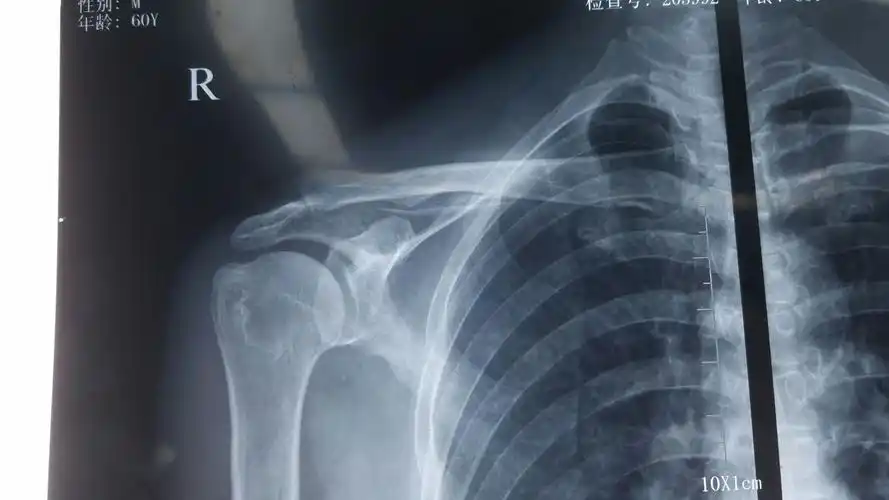

术前左肩关节正位片提示:左肱骨大结节处骨赘形成(肩峰撞击引起)

右肩关节间隙,肩峰下滑囊,喙突下滑囊少量积液.

肩峰撞击症肩袖损伤病例